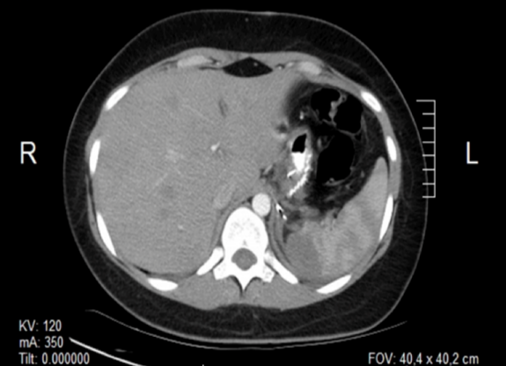

La paciente se mantiene asintomática por 21 días, cuando comienza a presentar febrícula 38°C y dolor lumbar izquierdo de moderada a fuerte intensidad. Al examen físico se evidencia signos vitales dentro de la normalidad; tórax sin alteraciones; abdomen blando, doloroso en hipocondrio izquierdo sin irritación peritoneal ni megalias. Laboratorio sin alteraciones (cuanta blanca normal). Se realizó ecosonograma y nueva TC de abdomen con los hallazgos de absceso esplénico en polo superior y barro biliar (Figura 3). Se intenta tratamiento médico con antibioticoterapia endovenosa (mismo esquema) sin respuesta a las 72 horas, por lo que se decidió intervención quirúrgica: esplenectomía y colecistectomía por laparoscopia, previa administración de profilaxis para gérmenes encapsulados (vacuna antineumocóccica polisacarídica y anti haemophylus influenzae tipo B).

Figura 3.

Absceso esplénico en el polo superior